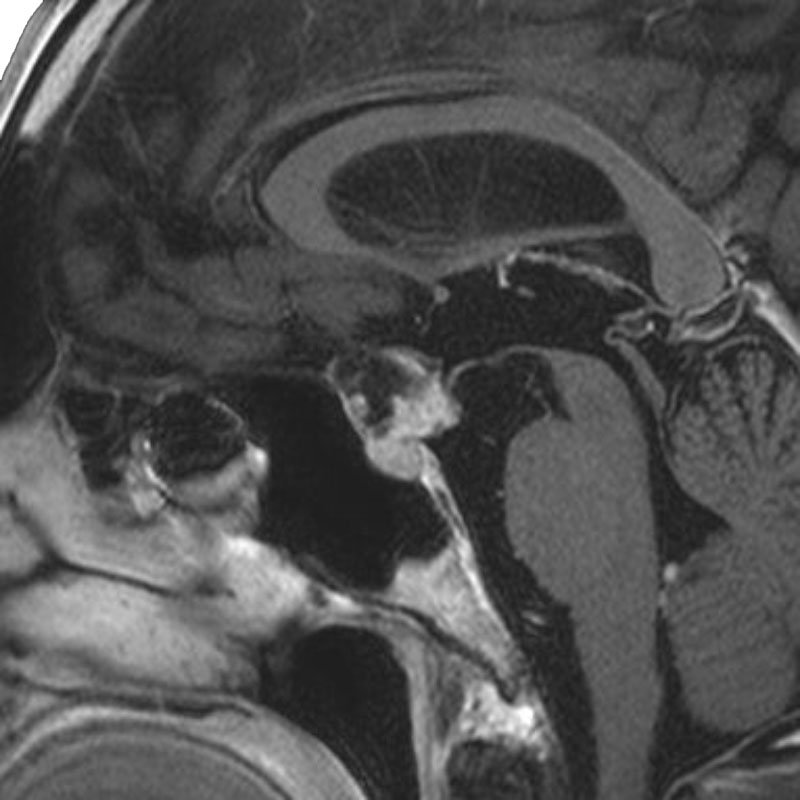

脳動脈瘤(Rt.IC-PC)

クリッピング術

乾/長尾/殿元/佐伯

脳動脈瘤(Lt.IC-PC)

松田/濵田